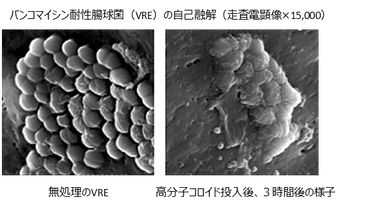

従来の抗菌・除菌剤は、薬理作用による細菌の組織合成阻害あるいは機能阻害をすることで効果を発揮する一方、細菌は抗菌成分を無効化する酵素を作り出すことなどで、耐性菌へと変化する可能性がありました。一方、本高分子コロイドは、細胞壁に物理的に吸着し細菌を自己融解に導くため、耐性菌発生のメカニズムとは無縁であり、耐性菌を生み出さず、多剤耐性菌にも有効です。【写真2】

【写真2】 http://www.atpress.ne.jp/releases/49976/img_49976_3.png